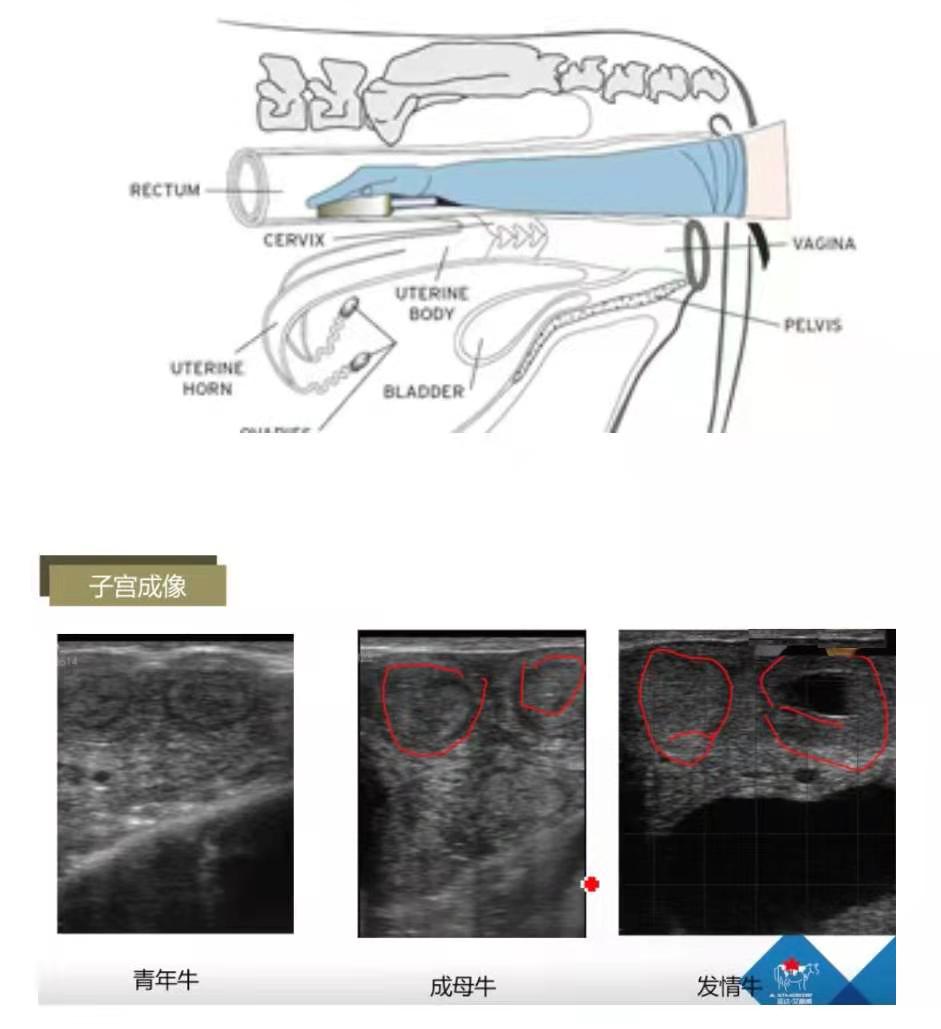

B超的现场操作:

开机并将目镜或屏幕调至适合状态

手握探头贴紧肠壁伸入直肠

到达子宫将探头横于子宫体确认图像

进一步确认延双侧子宫角下行

了解卵巢状况在子宫角大弯两侧确认图像

注意:①进入直肠时不清除宿粪,会耽误时间,而且会造成直肠强烈怒责,增加操作时间,造成判断失误;②探头横于子宫体。

子宫成像:青年牛子宫角直径1.5-2cm,灰色;成母牛子宫角直径2-4cm;发情牛一侧子宫角开张,子宫内膜增生,发情时子宫颈口和阴道分泌粘液,流入子宫,子宫角呈现黑色。